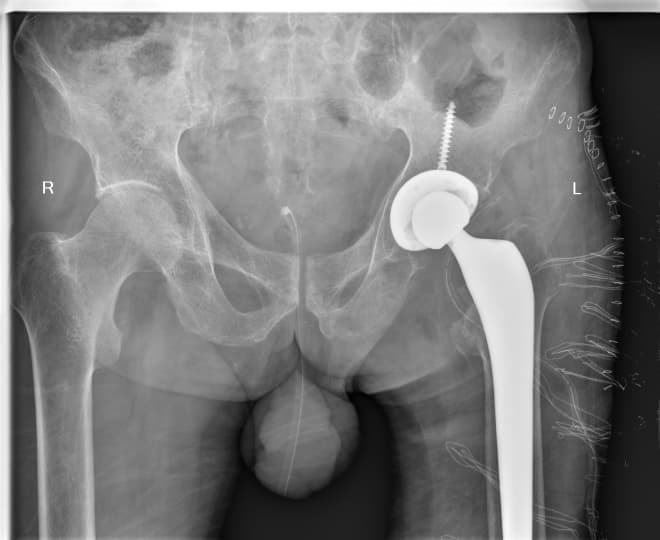

Дунд чөмөгний дээд хэсгийн /проксималь/ хавдар

Дунд чөмөгний проксималь буюу дээд хэсгийг хамарсан яс, зөөлөн эдийн гаралтай хавдрын улмаас түнхний үе, дунд чөмөгний дээд хэсгийг бүхлээр нь солих (мөч хадгалах мэс засал) мэс заслын эмчилгээг хийнэ.

Мэс заслын өмнөх болон дараах рентген зураг